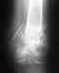

Компрессионный перелом L2 позвонка. |

Проконсультируйте, пожалуйста, о методах лечения, нет ли необходимости операции при компрессионном стабильном неосложненном переломе L2 позвонка. Так же имеется Диффузное выбухание м/п диска L4-L5(из заключения МРТ). Описание МРТ: Выявляются дистрофические изменения 1-й стадии в исследуемых сегментах в виде дегидрации ядер м/п дисков без уменьшения их высоты.Клиновидная деформация 1-й степени, отек тела L2 позвонка. Дуга позвонка не изменена. В сегменте L4-L5 диффузное выбухание м/п диска, переднезадним размером 3мм, с легкой деформацией передней поверхности дурального мешка и сужением м/п отверстий 1-й степени.Переднезадний размер позвоночного канала на уровне тела L4 позвонка 17мм. Каудальные сегменты спинного мозга и корешки "конского хвоста" не изменены. Паравертебральных изменений не выявляется.Заранее,СПАСИБО.